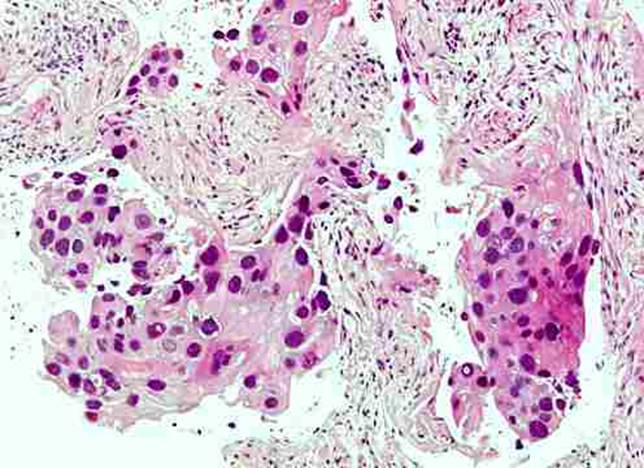

Děložní čípek po ozáření

Děložní čípek po ozáření.